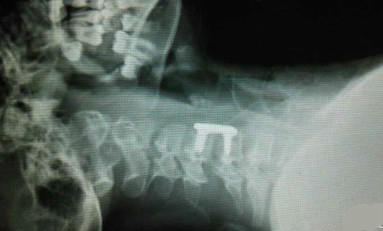

微信朋友圈,很多人都在為這位10歲的小姑娘祈禱。這就是她頸椎完全斷裂的圖片。

12月2日下午,她戴著長圍巾乘坐電動車時,長圍巾被車輪絞住。在慣性作用下,小青的脖子被緊緊勒住,電動車停下後,她感覺自己不能動了,而且呼吸也變得非常困難。經過手術,小青終於脫離危險,但由於脊柱斷裂,小青已全身癱瘓。同時,意外還影響到了肌肉,小青已不能自主呼吸,目前只能通過呼吸機輔助呼吸。